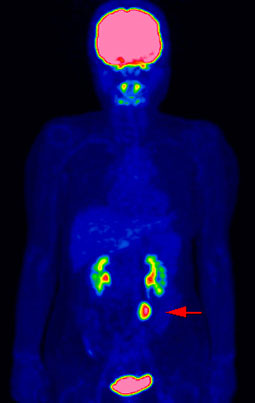

④がんの進行度、転移・再発の有無を確認できます

がんの恐いところは、離れた臓器に転移したり、治療しても再発してくる場合があることです。

しかもがんの転移や再発がどの臓器に出現するかを予測することは大変困難です。

一度の検査で全身をみることができるFDG-PET検査は、がんがどの程度まで拡がっているかといった、がんのステージを判断(病期診断)したり、思わぬ場所への転移や再発がないかどうかを調べるのに役立ちます。

これらを確認することは、その後の治療方法を決めるのにとても重要です。

PET検査による病状の把握で治療方針が変わることも少なくありません。

治療後経過観察にて以前の病変近傍に新たな病変出現(再発)